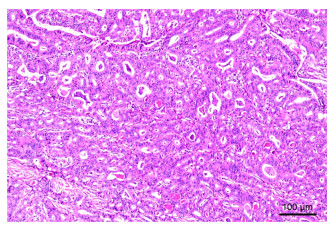

Application of BOPPPS combined with CBL teaching method in the reform of digestive system teaching in internal medicine

LIU Aiqun, GUO Xiaoyun, TANG Xiping, SHEN Yanhua, WEI Lining, ZHONG Yi, HUANG Yueli, XIE Weishun, ZHONG Dani

2025, 23(10): 1773-1776. doi: 10.16766/j.cnki.issn.1674-4152.004226

76 1

Abstract:

Objective  The BOPPPS model, characterized by its student-centered approach and emphasis on full student participation, is increasingly applied in classroom teaching. When combined with CBL (Case-Based Learning), teachers can adjust the teaching implementation according to classroom real-time feedback to achieve better teaching effects. Based on this situation, this study aimed to explore the practical application and effectiveness of the BOPPPS combined with CBL blended teaching mode in the teaching of digestive system-upper gastrointestinal bleeding, with the goal of informing future reforms in clinical teaching.  Methods  A total of 229 students majoring in clinical medicine from the School of Oncology, Guangxi Medical University in 2020, were selected as the research objects, and classes were randomly grouped using computer software to generate random numbers. They were randomly divided into the experimental group A (BOPPPS combined with CBL, 113 students) and the control group B (traditional mode teaching, 116 students). At the end of the teaching period, a combination of questionnaires and a theoretical knowledge examination was used to evaluate teaching effectiveness.  Results  The satisfaction survey showed that students in the experimental group were more satisfied with the overall course experience, course content, and teaching method than those in the control group (all P < 0.05). In the post-class examination, the scores in the experimental group was significantly higher than that of the control group, with significant differences(81.53±5.16 vs. 79.28±9.96, t=2.137, all P < 0.05).  Conclusion  In the context of digestive system teaching, the BOPPPS combined with CBL blended teaching demonstrates greater effectiveness than the traditional method. It promotes students ' engagement and participation, and is well-suited for promotion and application in the clinical teaching of internal medicine.